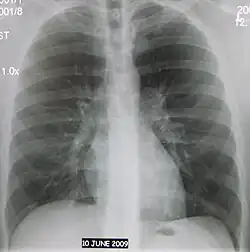

Abreugrafia, microrradiografia, fotofluorografia ou fluorografia é uma fotografia de pequena dimensão de um ecrã de fluoroscopia ou radioscopia, usada no rastreio em massa de tuberculose.[1] O método foi criado pelo professor e médico brasileiro Manuel Dias de Abreu em meio à epidemia de tuberculose que assolava a cidade do Rio de Janeiro nas primeiras décadas do século XX.[2][3] Trata-se de uma radiografia em tamanho reduzido dos pulmões a partir de um método rápido e de baixo custo com o objetivo de facilitar o diagnóstico daquela doença que levava a altos índices de mortalidade à época.[2][4]